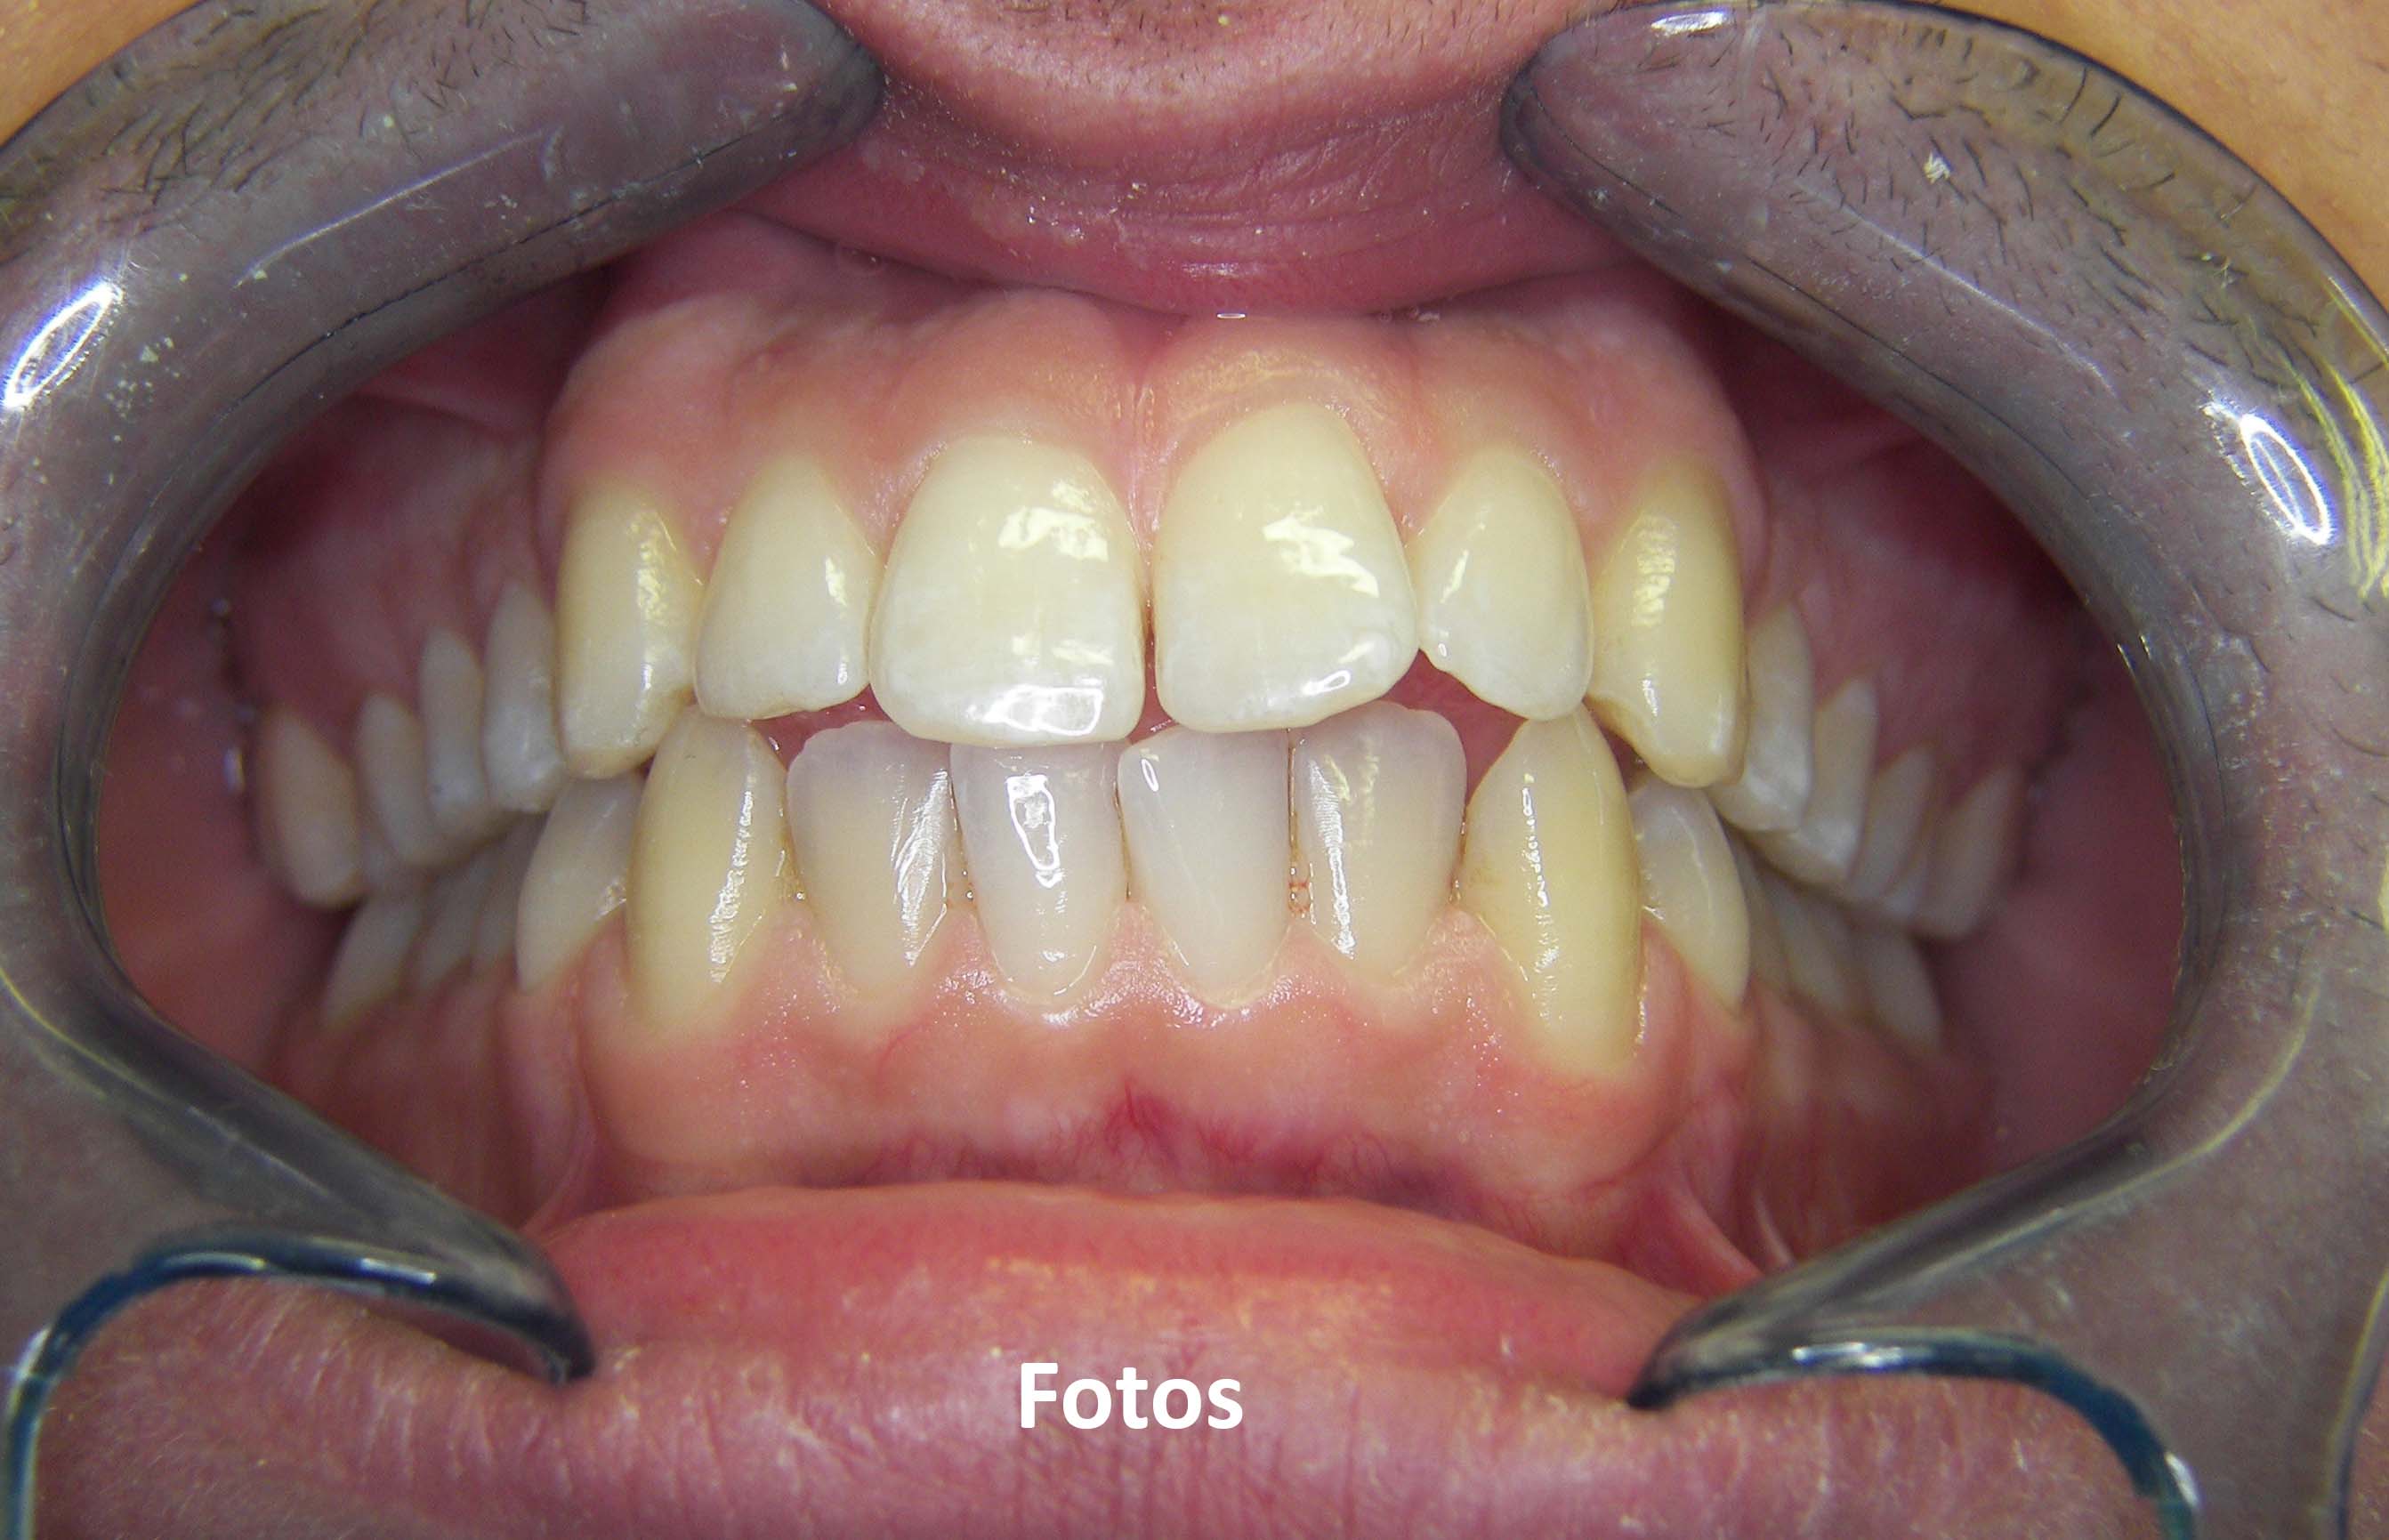

Casos clínicos

3. Fotografias

Tratamentos urgentes serão executados se necessário, como no caso à esquerda.

SOS